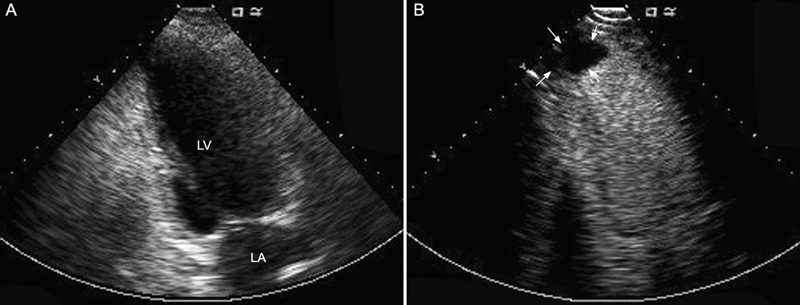

فحوصات تشخيصية لبعض امراض القلب والشرايين التاجية